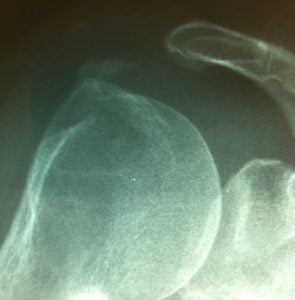

Calcification Amorphe

La trituration lavage infiltration est une intervention mini invasive indiquée dans les calcifications intra-tendineuses de l’épaule. Ces calcifications sont liées à une accumulation de cristaux d’hydroxyapatite. Ces calcifications sont le plus souvent asymptomatiques mais peuvent devenir tres douloureuses en cas d’inflammation.

Il consiste sous anésthésie locale à l’introduction de 2 aiguilles au niveau de la calcification. Cette procédure est réalisée sous contrôle radiologique et/ou échographique. Le médecin réalise dans un premier temps une fragmentation de la calcification à l’aide des aiguilles. Puis un lavage au serum physiologique permet ensuite d’aspirer une substance laiteuse, calcique correspondant à l’extraction de la calcification. En fin d’intervention une infiltration de la bourse sous acromio deltoidienne est réalisée afin de diminuer l’inflammation.

Une douleur résiduelle peut être resentie pendant quelques jours. Un contrôle à un mois par radiographie simple ou echographie peut être réalisée en cas de persistance des douleurs. Les récidives ne sont pas rares et doivent faire rechercher une anomalie métabolique.